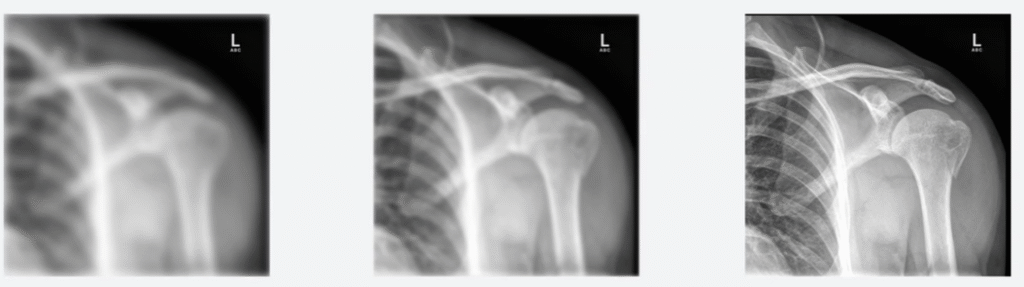

π‘Definition: Resolution (also known as spatial resolution) describes how well small details can be distinguished on a radiograph. High-resolution images show clear structures with defined edges, while low-resolution images appear blurry.

π We can see that the first image (low resolution) appears very blurry, and the edges are not sharp at all. The middle image has increased spatial resolution. The end image has the highest spatial resolution, where we can distinguish the fine details.

Image Souce – Clover Learning